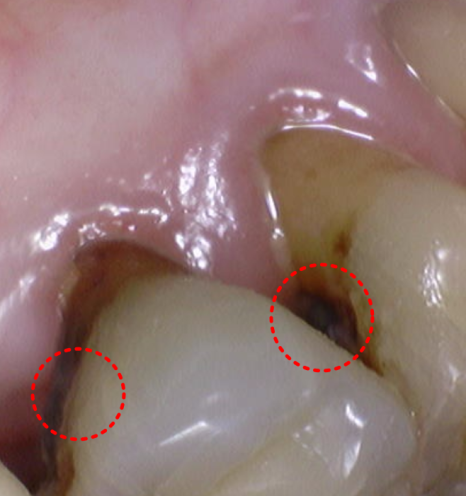

확인해 보니

이전에 말씀드린 앞니 쪽이 문제였죠.

240404

1년 전보다 상태가 더

진행돼 있었는데요.

충치가 오래 누적되면서

치아는 사실상 뿌리만 남은 상태였고,

치아 뿌리도 흡수가 진행돼

짧아져 있었습니다.

이런 경우는 기둥을 넣어

보철을 새로 만들더라도

오래 쓰지 못할 가능성이 높습니다.

확인해 보니 이번에도

충치 범위가 넓고

뿌리가 짧아진 상태라

보존적으로 살리기

어렵다고 판단했습니다.